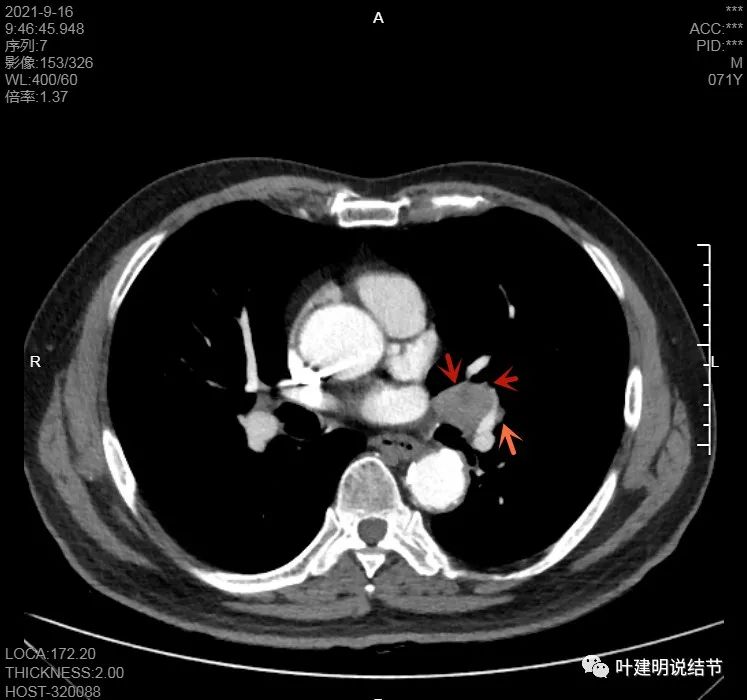

上图示主病灶边缘非常光滑,膨胀性不明显

上图似乎边缘有点磨玻璃,但这可能是病灶横断面扫到组织相对较少或较薄的地方,其实并不是磨玻璃成分